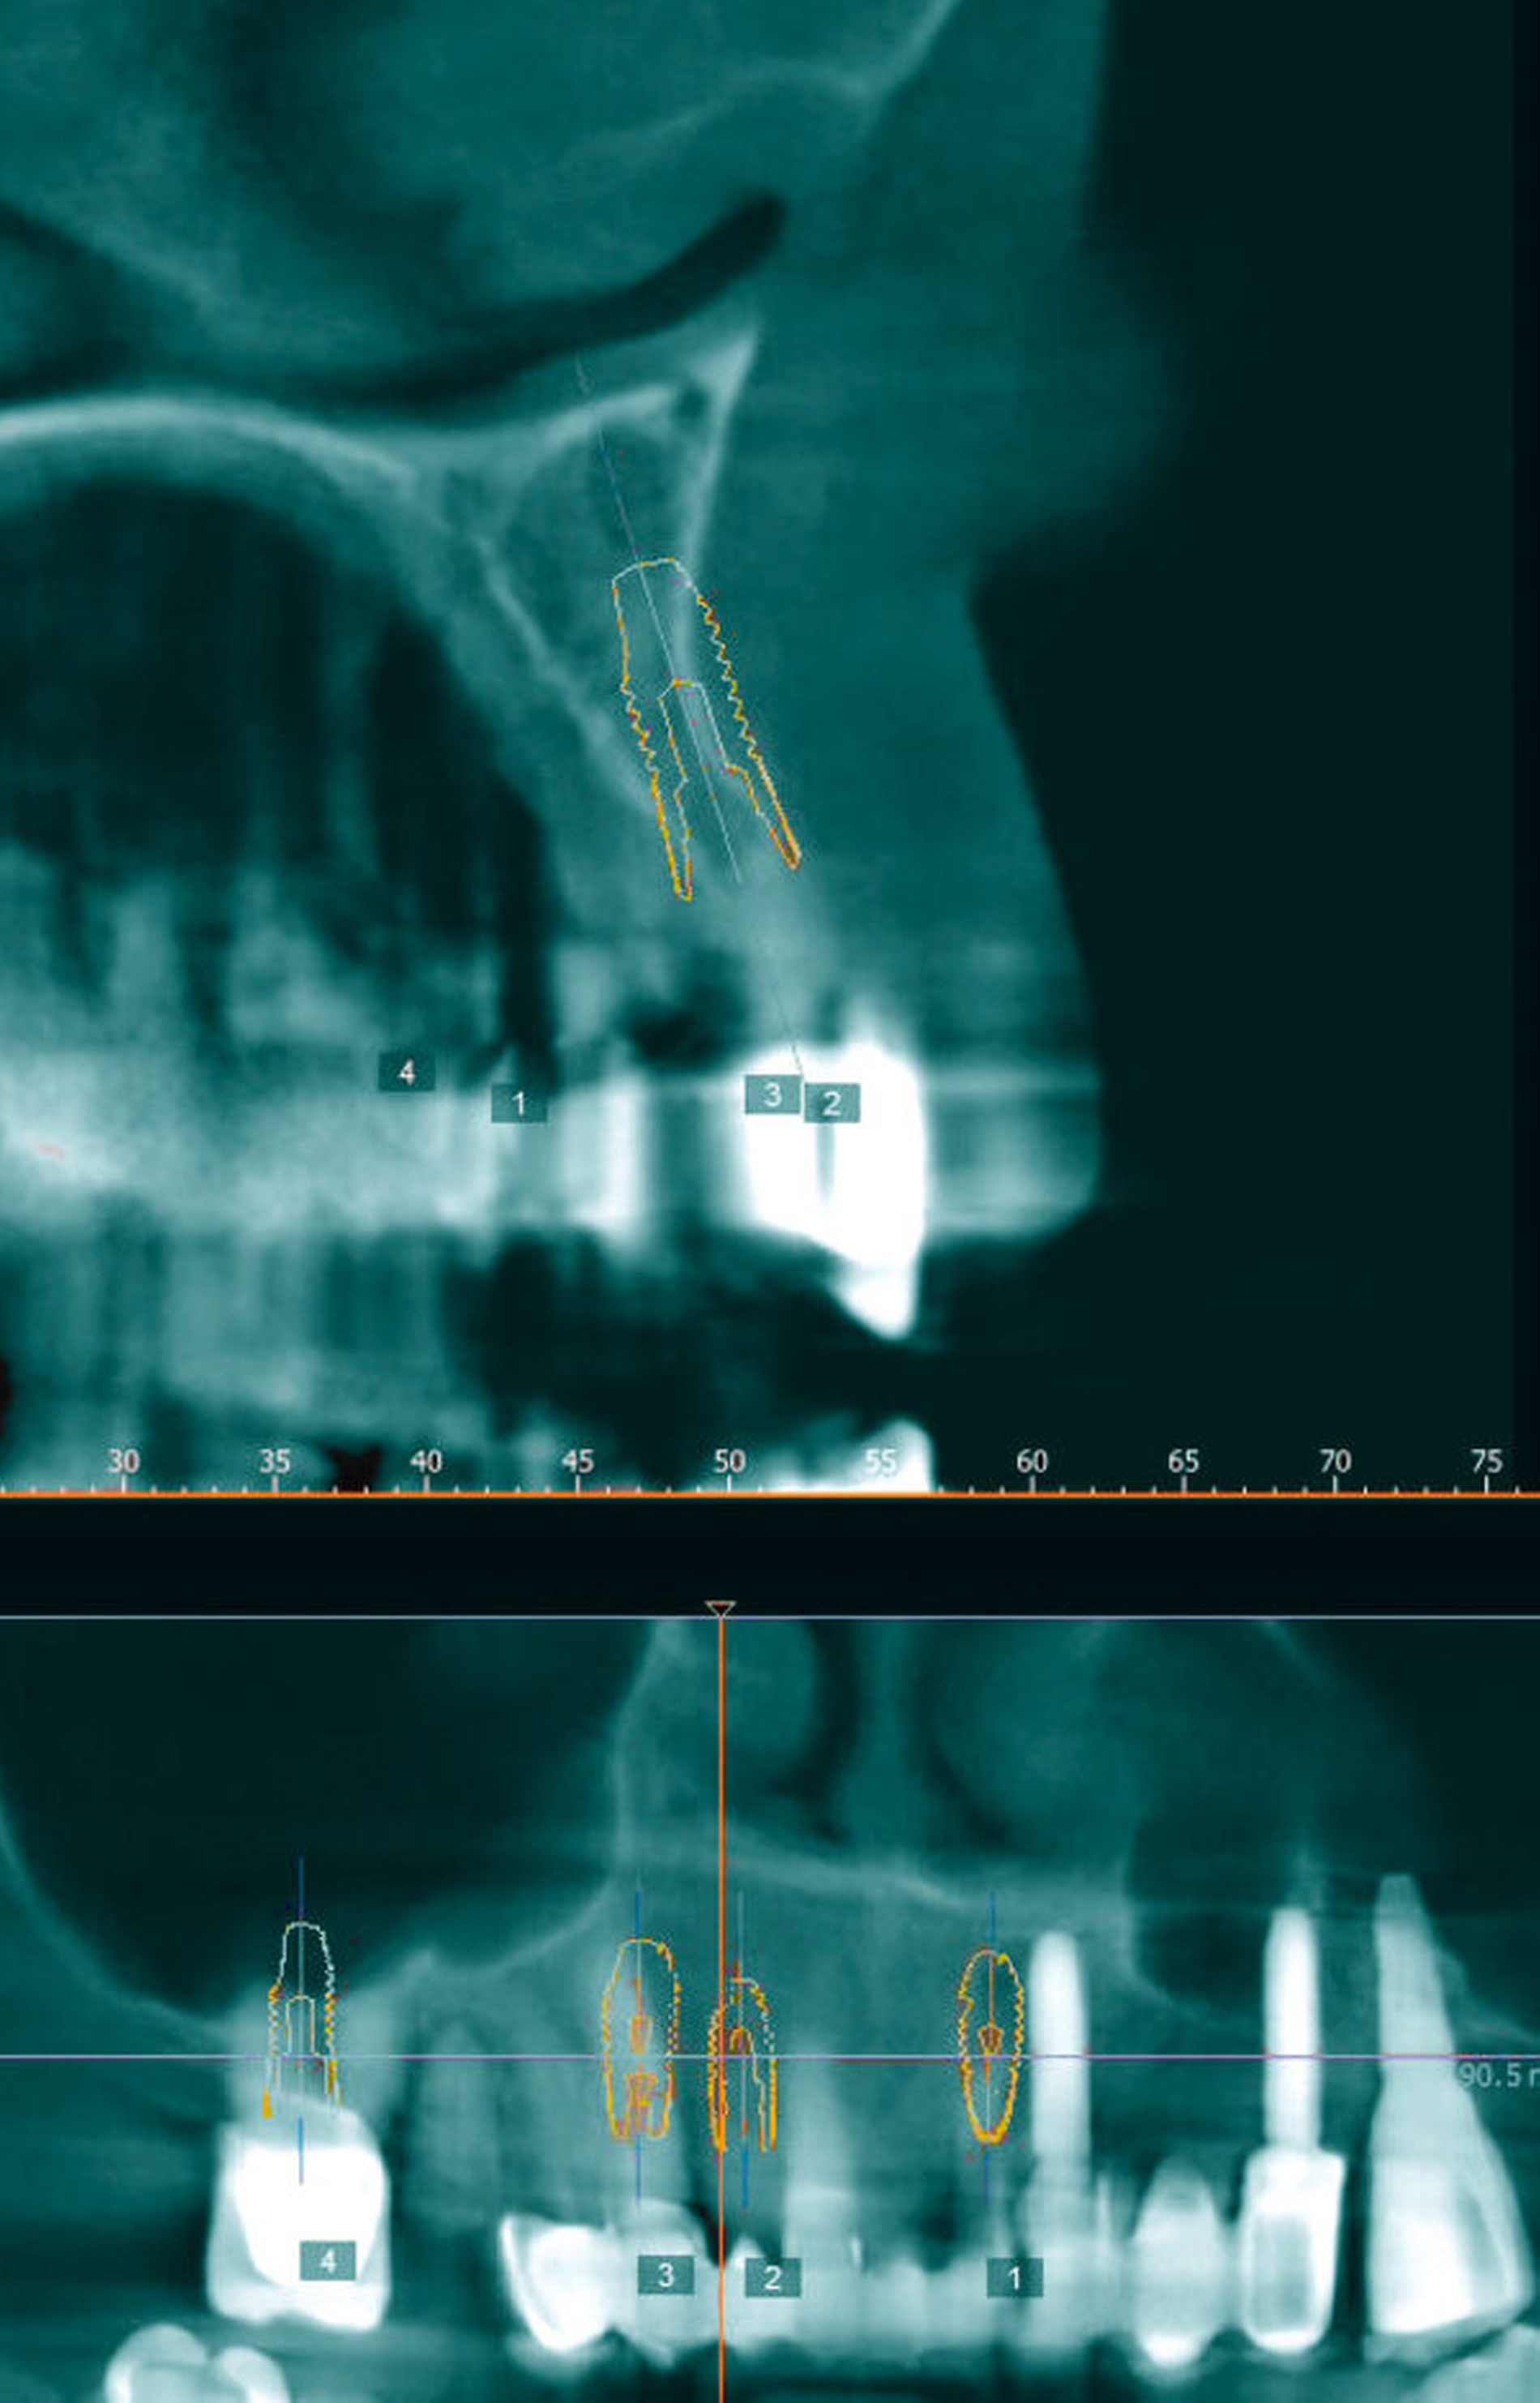

In der Panoramaschichtaufnahme (Abbildung 1) zeigte sich zusätzlich eine insuffiziente Wurzelkanalbehandlung am Zahn 16 mit einer Obliteration der nicht gefüllten buccalen Kanäle. An den Zähnen 11 und – insbesondere – 22 war ein Attachmentverlust sichtbar. Zur besseren Beurteilbarkeit der vorliegenden Knochensituation wurde eine digitale Volumentomografie angefertigt. In dieser zeigten sich horizontale Knochendefekte regio 15–22 sowie ein vertikales Knochendefizit in regio 16 (Abbildung 2).